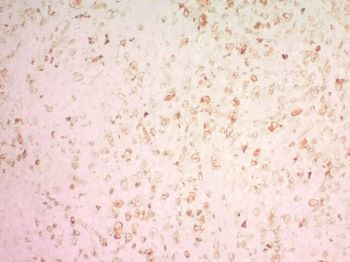

Sections of the lymph node show complete effacement of the lymph node architecture by atypical large cells with irregular nuclei, prominent nucleoli and abundant cytoplasm. Occasional large hallmark cells showing eccentric kidney-shaped nuclei are recognized. Mitoses are readily recognized, along with abundant apoptotic bodies. The background show many inflammatory cells that include small lymphocytes, plasma cells, neutrophils, and eosinophils. The atypical cells exhibit strong, diffuse reactivity for CD30 with membranous and Golgi area staining. The large atypical cells are positive for EMA and CD5 and appear to be negative for CD15, CD3, CD2, CD20, PAX5, and BCL2. ALK staining highlights a large subset of atypical large cells.